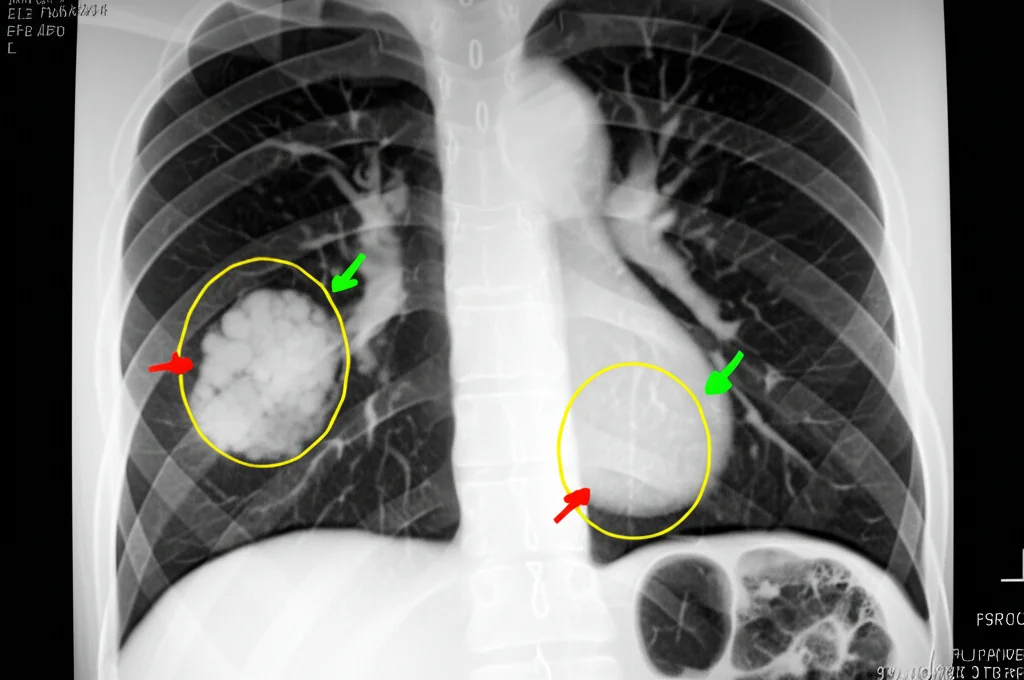

Vi presento il protagonista (involontario) di questa storia: un signore di 66 anni. Per un mese intero, combatte con tosse, catarro, senso di oppressione al petto e un calo di peso che non promette nulla di buono. Va dal medico, prova antibiotici (cefaclor, azitromicina), ma niente, i sintomi restano. Fa una radiografia al torace e… sorpresa: si vede una “lesione occupante spazio” nel polmone sinistro. Tradotto: una massa. Viene ricoverato per capirci di più. Gli esami del sangue sono a posto, ma la TAC è più dettagliata e mostra non una, ma due masse irregolari di tessuto molle nel polmone sinistro, una nel lobo superiore e una in quello inferiore. Queste masse hanno contorni frastagliati, sembrano “infiltrarsi” nel tessuto circostante (spiculazioni) e tirare la pleura (la membrana che riveste i polmoni). Insomma, l’aspetto è proprio quello che fa drizzare le antenne per un possibile cancro al polmone. Per aggiungere sospetto a sospetto, una PET-CT (un esame che valuta il metabolismo delle cellule) mostra che queste lesioni “bruciano” molto glucosio, un altro segnale tipico dei tumori. Anche i linfonodi vicini appaiono ingrossati. A questo punto, l’ipotesi principale sul tavolo è una sola: tumore polmonare.

Di fronte a un quadro così sospetto, la mossa successiva è quasi obbligata: bisogna prendere un pezzettino di quel tessuto e analizzarlo al microscopio. Si procede quindi con una biopsia polmonare percutanea guidata dalla TAC sulla massa del lobo superiore. E qui arriva il colpo di scena. L’analisi istologica rivela che le cavità alveolari sono piene di un materiale simile a fibrina (una proteina coinvolta nella coagulazione) e infiltrate da tantissime cellule infiammatorie. Niente cellule tumorali. La diagnosi patologica è chiara: AFOP. Ma aspettate, non è così semplice. I medici sono cauti: la biopsia prende solo un piccolo campione, e se avessero “mancato” la parte tumorale? Dopo una discussione tra vari specialisti, il sospetto di cancro rimane. Si decide per una seconda biopsia, questa volta prelevando campioni da entrambe le masse, sia quella superiore che quella inferiore. Il risultato? Di nuovo AFOP. Si vedono chiaramente l’essudato di fibrina negli alveoli, tessuto connettivo giovane (fibroblasti), tanti neutrofili e linfociti (cellule dell’infiammazione). Nessuna traccia di tumore. A questo punto, con due biopsie concordi, la diagnosi di AFOP sembra solida.